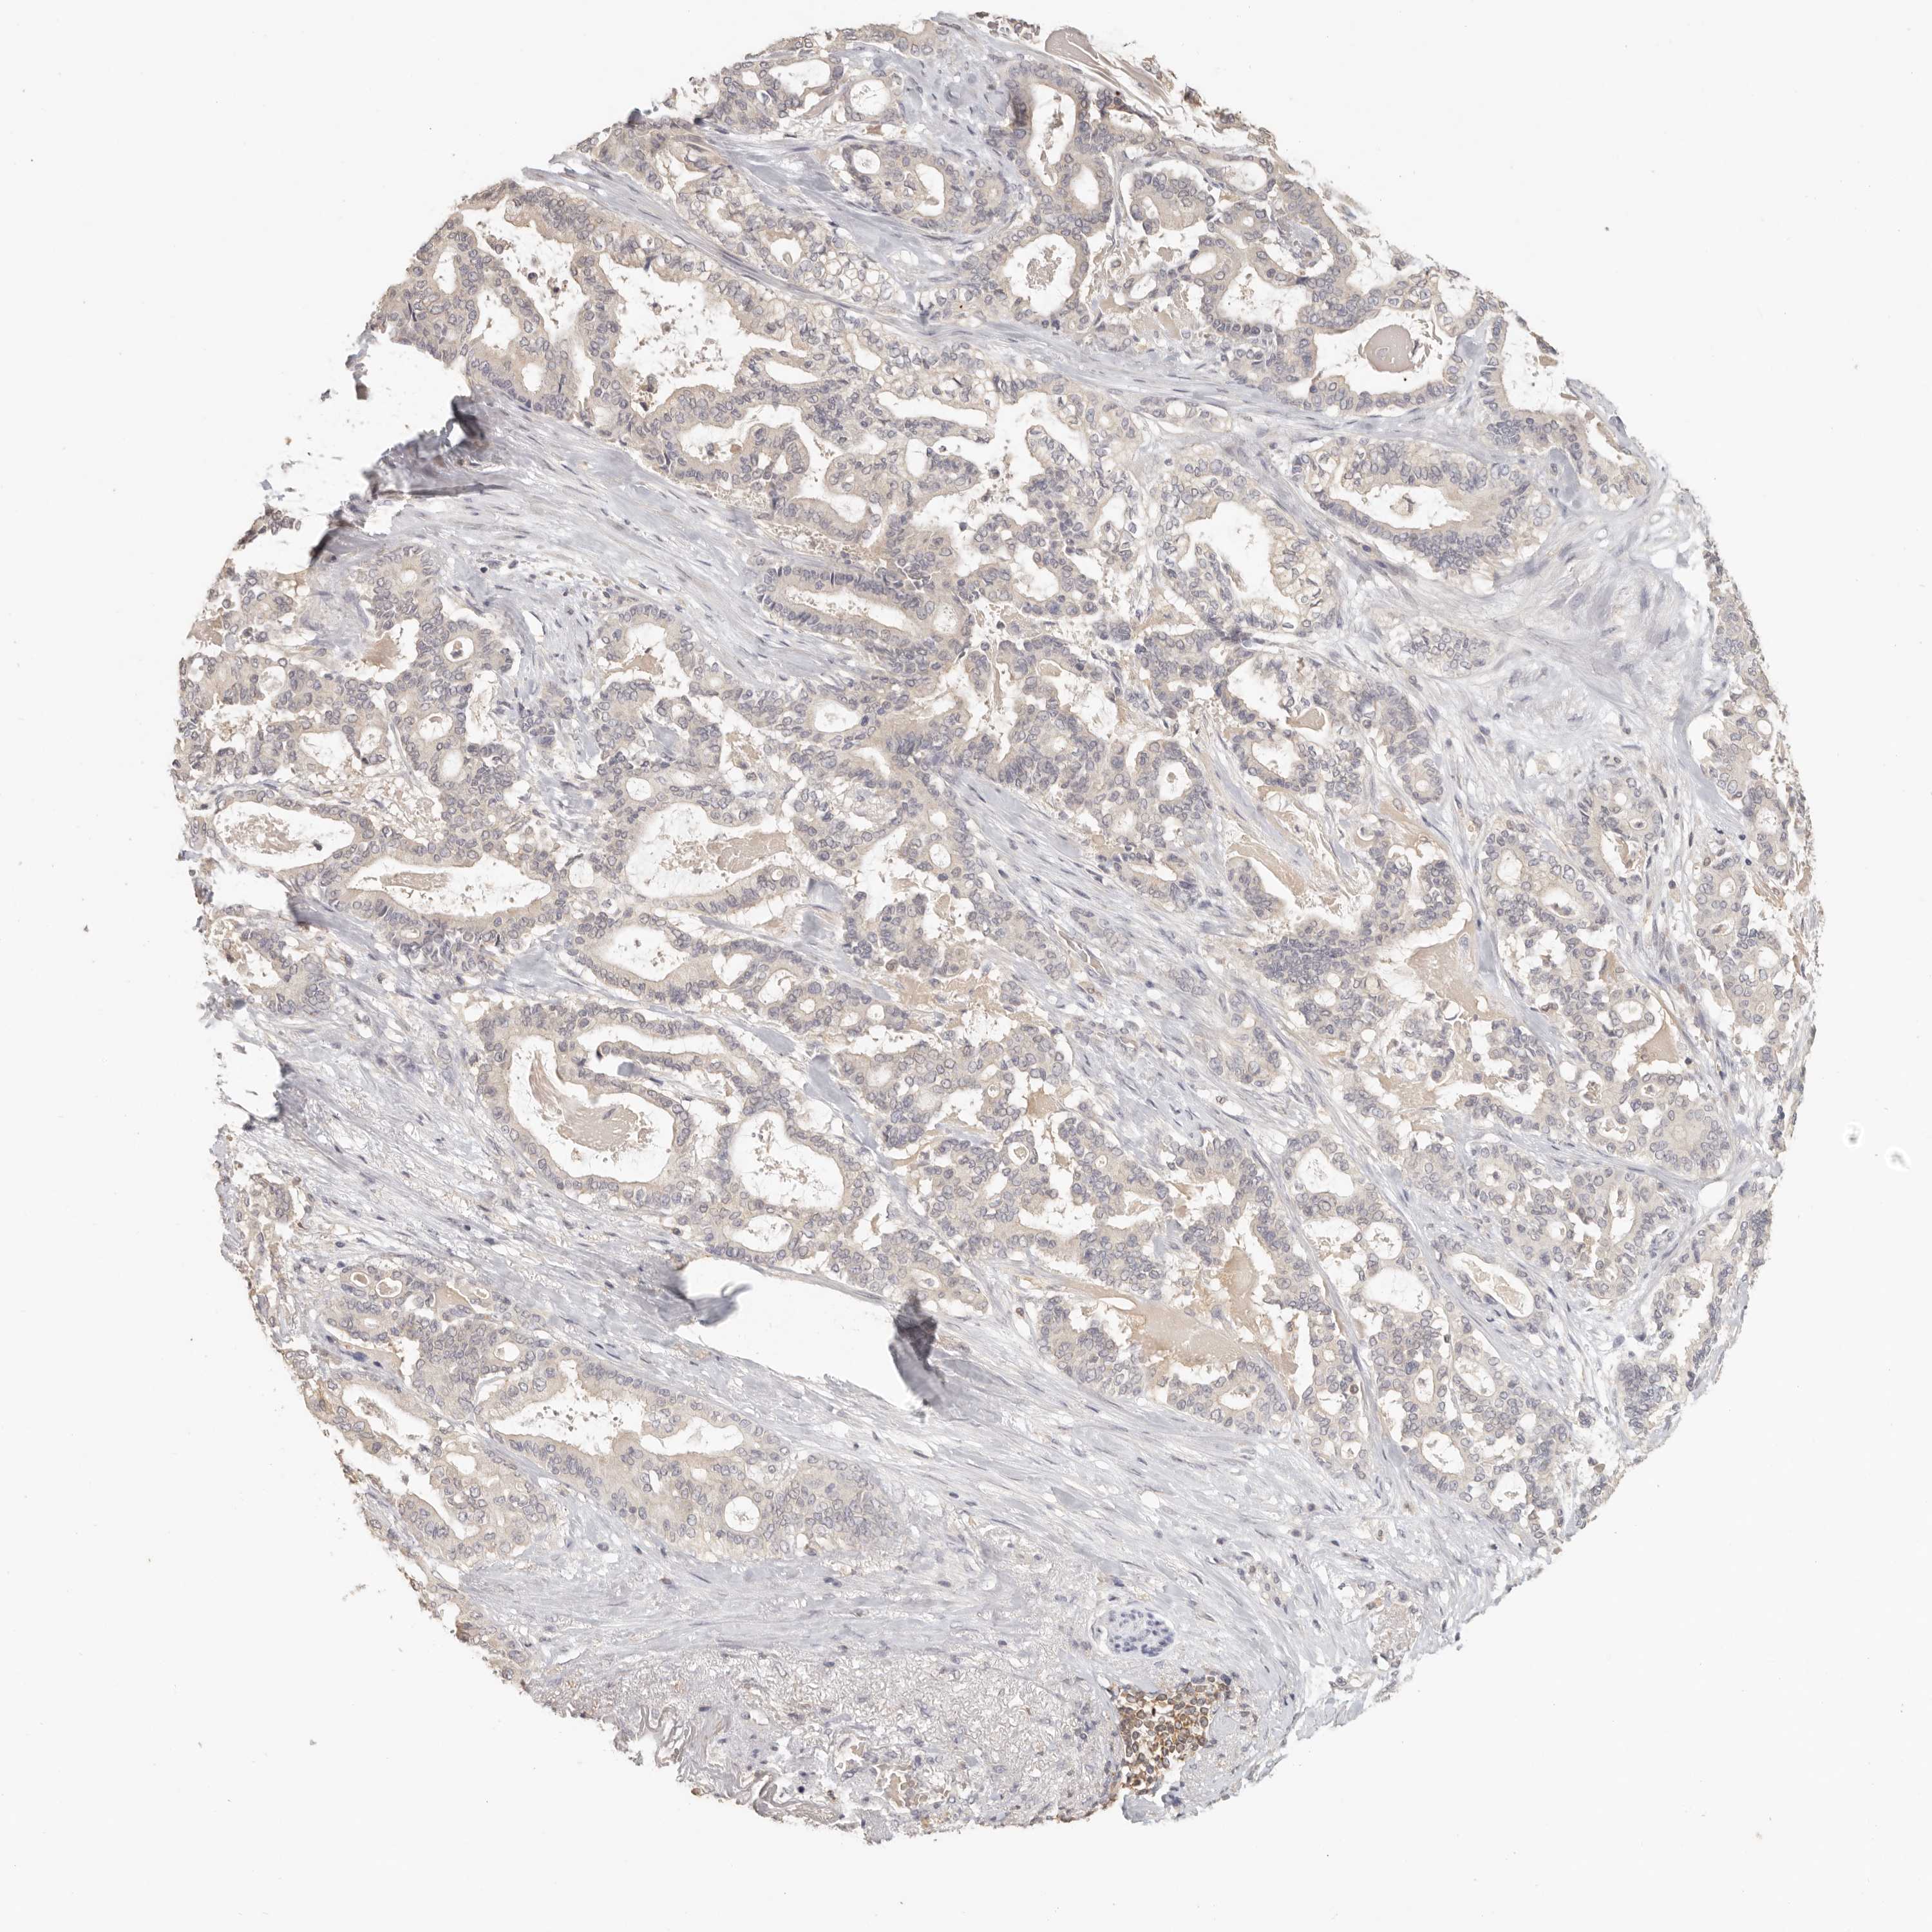

PANCREATIC CANCER - Protein expressioni

A mouse-over function shows sample information and annotation data. Click on an image to view it in a full screen mode. Samples can be filtered based on level of antibody staining by selecting one or several of the following categories: high, medium, low and not detected. The assay and annotation is described here.

Note that samples used for immunohistochemistry by the Human Protein Atlas do not correspond to samples in the TCGA dataset.

Antibody stainingi

Antibody staining in the annotated cell types in the current human tissue is reported as not detected, low, medium, or high, based on conventional immunohistochemistry profiling in selected tissues. This score is based on the combination of the staining intensity and fraction of stained cells.

Each image is clickable and will lead to virtual microscopy that enables deeper exploration of all samples and also displays staining intensity scores, fraction scores and subcellular localization as well as patient and tissue information for each sample.

Antibody HPA026488

Antibody HPA028425

Antibody CAB011203

Staining

High

Medium

Low

Not detected

Intensity

Strong

Moderate

Weak

Negative

Quantity

>75%

75%-25%

<25%

None

Location

Nuclear

Cytoplasmic/membranous

Cytoplasmic/membranous,nuclear

Adenocarcinoma, NOS

Adenocarcinoma, metastatic, NOS